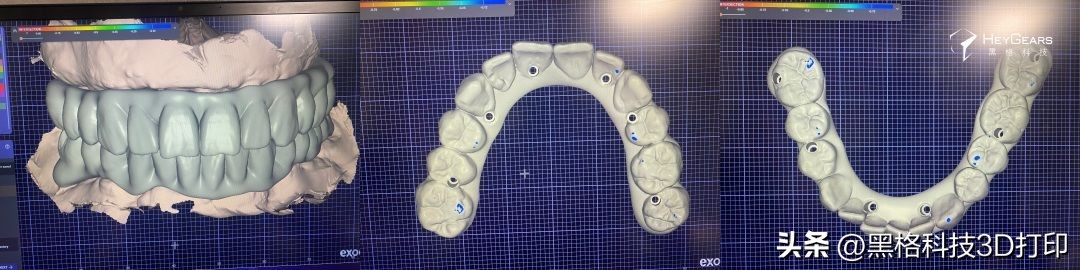

▲术前3D扫描图像

1)种植临时义齿设计

患者对于美观性有着较高需求,在外科手术后结束后,根据患者骨质情况以及初期稳定性确定可进行即刻修复。在植体植入后安装临时基台,通过再次数据扫描,获取精准数据,从而设计、制作更精准种植临时义齿。

▲种植临时义齿设计方案